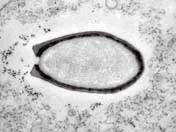

a–2æ3•国科å-|家复æ′»çš„一种在西ä¼ˉ利äošæ°¸ä1…冻土ä¸-冷冻äo†3万多å1′的巨型无å®3ç—…æˉ’

▲法國科學(xué)家復(fù)活的一種在西伯利亞永久凍土中冷凍了3萬多年的巨型無害病毒

2014年3月,科學(xué)家在俄羅斯的西伯利亞凍土層中發(fā)現(xiàn)了迄今世界上最大的巨型病毒,長達(dá)1.5微米,科學(xué)家將其命名為“西伯利亞闊口罐病毒”。

法國艾克斯·馬賽大學(xué)的進(jìn)化生物學(xué)家簡-米歇爾·克拉弗認(rèn)為,永久凍土里面溫度很低,不含氧氣且處于黑暗中。因此,下層永凍土中可能仍保存著能感染人類或動物的病毒,包括過去曾引發(fā)全球性傳染病的致病性病毒。